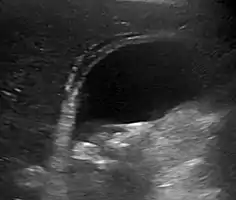

Abdominal ultrasonography showing gallstones, wall thickening and fluid around the gall bladder

Gallstones and biliary sludge, but the gallbladder wall is not clearly thickened, with no edema in the pericholecystic fat, thus not cholecystitis.